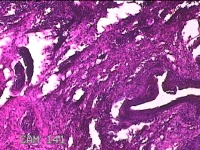

腰背部结节

性别

男

年龄

51岁

临床诊断

躯干皮脂腺囊肿

一般病史

发现腰背部结节20余年,伴近日局部隐痛不适及少许渗出。

标本名称

大体所见

灰白暗红色结节1.8x0.5x0.3cm一个,表面糜烂,切面灰白暗红色,质软。